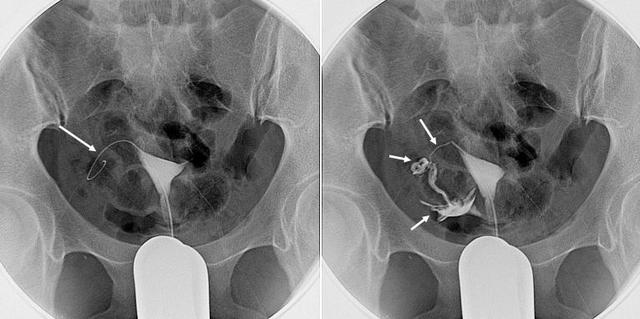

输卵管再通术进行中,右侧再通成功

首先,医生会经过严格的清洁消毒,从阴道向子宫腔送入介入治疗器械,在电视透视下进行子宫和输卵管造影;明确阻塞部位后,就要送入纤细光滑、具有一定刚度和柔软度的导丝对阻塞处进行反复轻柔的机械疏通。再次造影确认再通成功后,应经导管向输卵管内注入输卵管疏通液,以加强治疗效果并防止再闭塞。一侧成功后,同法再进行另一侧治疗。

输卵管再通术进行中,左侧再通成功